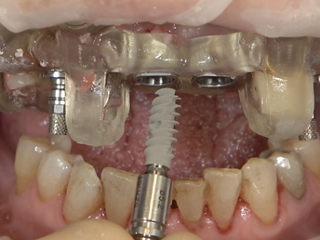

Guided FP1 maxillary rehabilitation with Straumann® STARconcept™ and Straumann iGuide™. A clinical case report by Dr. David Norré, Belgium.

Facially driven Smilecloud design with a focus on preserving tissue and bone. Planned in Smile in a Box and executed with the iGuide protocol; shared pin positions align the drill and prosthetic guides for chairside pickup of the pre-designed provisional. Day-5 follow-up shows the screw-retained provisional in place.

• Fully guided implant insertion using the iGuide® implant driver with vertical stop.

• Implant drivers left engaged to stabilize the guide; fixation pins drilled precisely.

• Extraction of remanning teeth and placement of straight SRAs.

• Temporary Copings for SRAs placed – ready for bridge pick-up.

• Temporary bridge pre-fit check using the prosthetic guide and fixation pins.